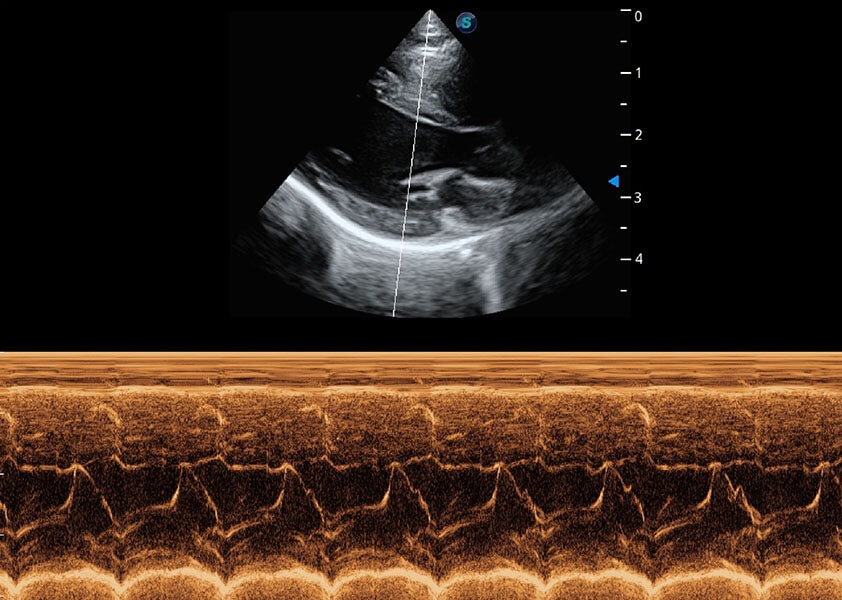

ProPet 60 作为一款高端台式动物超声设备,为动物医生的日常诊断提供了一系列贴合动物临床需求、解决临床实际问题的高级成像功能。凭借全系列高清探头,满足医生对腹部、心脏、生殖、浅表、肌骨等成像的所有需求,切实帮助您提升检查效率,提高诊断信心。

动物是人类最亲密的朋友和最值得信赖的伙伴。16877太阳集团也一直致力于探索动物专用的超声影像解决方案。 全新推出的ProPet系列,是16877太阳集团在动物超声影像智能化、专业化、精准化的一次跨越式革新。动物不能用言语来表述自己的不适,通过超声影像,ProPet系列搭建了动物医生与不同物种沟通的“桥梁”,为动物医生注入了“治愈之力”。